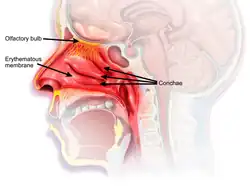

The nasal mucosa lines the nasal cavity. It is part of the respiratory mucosa, the mucous membrane lining the respiratory tract.[1][2] The nasal mucosa is intimately adherent to the periosteum or perichondrium of the nasal conchae. It is continuous with the skin through the nostrils, and with the mucous membrane of the nasal part of the pharynx through the choanae. From the nasal cavity its continuity with the conjunctiva may be traced, through the nasolacrimal and lacrimal ducts; and with the frontal, ethmoidal, sphenoidal, and maxillary sinuses, through the several openings in the nasal meatuses. The mucous membrane is thickest, and most vascular, over the nasal conchae. It is also thick over the nasal septum where increased numbers of goblet cells produce a greater amount of nasal mucus. It is very thin in the meatuses on the floor of the nasal cavities, and in the various sinuses. It is one of the most commonly infected tissues in adults and children. Inflammation of this tissue may cause significant impairment of daily activities, with symptoms such as stuffy nose, headache, mouth breathing, etc.

Owing to the thickness of the greater part of this membrane, the nasal cavities are much narrower, and the middle and inferior nasal conchæ appear larger and more prominent than in the skeleton; also the various apertures communicating with the meatuses are considerably narrowed.

The epithelium of the nasal mucosa is of two types – respiratory epithelium, and olfactory epithelium differing according to its functions. In the respiratory region it is columnar and ciliated.[3][4] Interspersed among the columnar cells are goblet or mucin cells, while between their bases are found smaller pyramidal cells. Beneath the epithelium and its basement membrane is a fibrous layer infiltrated with lymph corpuscles, so as to form in many parts a diffuse adenoid tissue, and under this a nearly continuous layer of small and larger glands, some mucous and some serous, the ducts of which open upon the surface. In the olfactory region the mucous membrane is yellowish in color and the epithelial cells are columnar and non-ciliated; they are of two kinds, supporting cells and olfactory cells. The supporting cells contain oval nuclei, which are situated in the deeper parts of the cells and constitute the zone of oval nuclei; the superficial part of each cell is columnar, and contains granules of yellow pigment, while its deep part is prolonged as a delicate process which ramifies and communicates with similar processes from neighboring cells, so as to form a net-work in the mucous membrane. Lying between the deep processes of the supporting cells are a number of bipolar nerve cells, the olfactory cells, each consisting of a small amount of granular protoplasm with a large spherical nucleus, and possessing two processes—a superficial one which runs between the columnar epithelial cells, and projects on the surface of the mucous membrane as a fine, hair-like process, the olfactory hair; the other or deep process runs inward, is frequently beaded, and is continued as the axon of an olfactory nerve fiber. Beneath the epithelium, and extending through the thickness of the mucous membrane, is a layer of tubular, often branched, glands, the glands of Bowman, identical in structure with serous glands. The epithelial cells of the nose, fauces and respiratory passages play an important role in the maintenance of an equable temperature, by the moisture with which they keep the surface always slightly lubricated.[4]